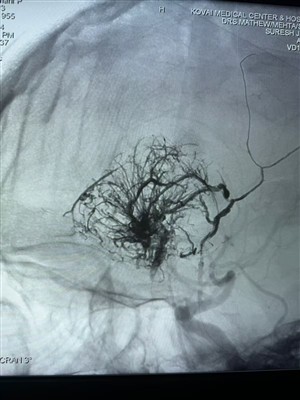

Cás AVM nua a d'úsáid gníomhaire embolic leachtach lava leachtachComhroinn cás nua AVM a úsáidtear gníomhaire embolic leachtach lava ó NeuroSafe Medical Co., Ltd. Seo a leanas an íomhá:

An Chéad Chás Meall Hipirshoithíoch Tuairiscithe san IndiaSásta an chéad chás meall hypervascular seo a dhéantar san India a roinnt. Cóireáladh é le Lava Leacht Embolic System ó NeuroSafe Medical Co., Ltd. Buíochas leis an Dr. Mathew Cherian. Bhí sé ina c...